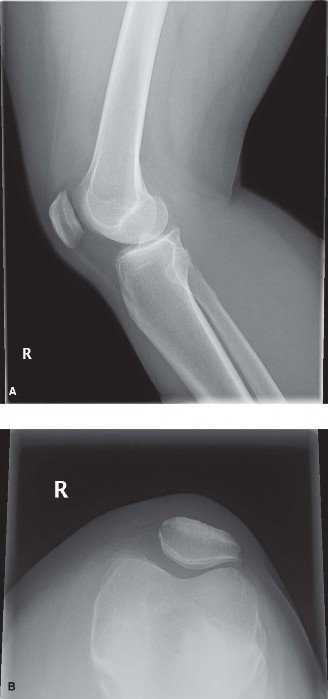

CASE 4 A 54-year-old skier injures his right knee on the last run of the day. …